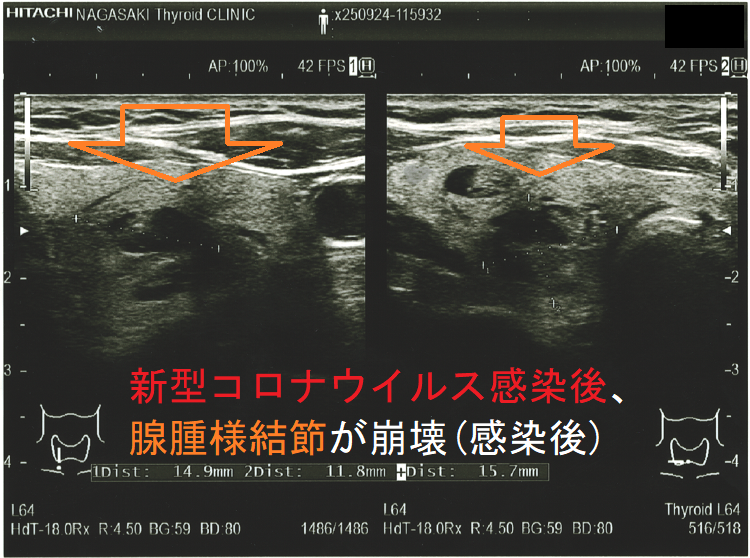

新型コロナウイルス感染(COVID-19)後、腺腫様結節が崩壊(感染後);感染後、内部は崩壊し、亀裂部に液体が充満。のう胞型腺腫様結節(嚢胞型腺腫様結節)のようになってしまった。